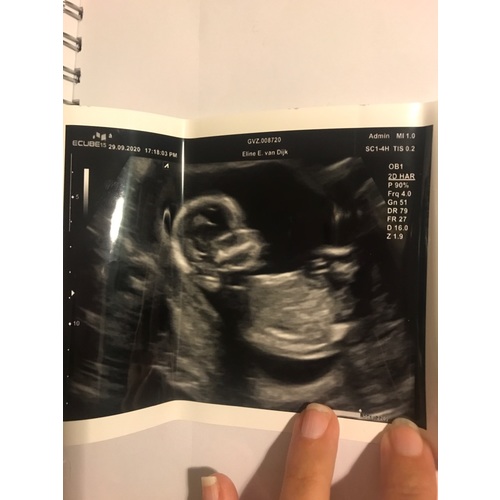

Bij 13w en 5 dagen zag je het ook vanaf zijkant en deze echo is 14w en 6 dagen

Ik was daar 14 weken en 6 dagen😊

Dit is mijn echo foto van vandaag, mijn vriendinnen heb ik een envelop gegeven met het geslacht en ik weet het zelf ook niet. Vraag me ook af of mensen het geslacht kunnen zien na aanleiding van deze echo.